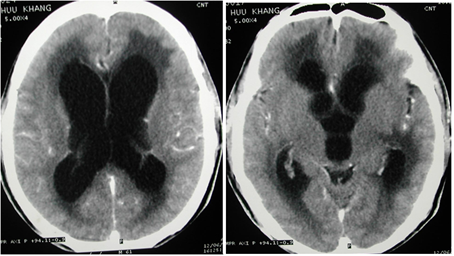

2. Chụp cắt lớp vi

tính sọ não

- đôi khi thấy nguyên nhân của TALNS:

+ Gây đè đẩy não thất vào đường giữa.

+ Phù não: Mất các rãnh não và giảm tỷ trọng quanh ổ tổn thương.

+ Não úng thủy do tắc nghẽn: Giãn não thất phía trên chỗ tắc.

+ Đánh giá ảnh hưởng của tăng áp lực nội sọ xem có thoát vị không.

+ Giúp cho điều trị tùy theo nguyên nhân.

hình ảnh giãn não thất

hai bên:

hình ảnh tổn thương

áp xe não

Hình ảnh tổn thương u tiểu não gây giãn não thất

hình ảnh tổn thương dạng

viêm não